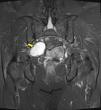

MétodosRealizamos un análisis retrospectivo de 19 casos de tumores neurogénicos de la región sacra diagnosticados y operados en nuestro centro, de los cuales ocho eran hombres y 11 mujeres, registrando una edad media al diagnóstico de 51 años (con un rango de edades entre 25 y 78 años). Seis se encontraban asintomáticos y fueron diagnosticados incidentalmente, mientras que la mayoría (11 pacientes) presentaban dolor lumbar acompañado de otros síntomas: dolor irradiado a miembros inferiores (MMII), dolor pélvico, alteraciones sensitivas y pérdida de fuerza en MMII. Dos pacientes presentaban otro síntoma principal al diagnóstico: dolor pélvico y en miembro inferior izquierdo (MII). A todos los pacientes se les realizó como mínimo una prueba de imagen (RM/TC). Nueve pacientes tenían tumores limitados al sacro o con extensión posterior, practicándose una intervención por vía posterior. En seis se realizó un abordaje exclusivamente por vía anterior debido a la localización presacra de la tumoración; y en cuatro de ellos fue preciso un abordaje tanto anterior como posterior.

MethodsWe conducted a retrospective analysis of 19 cases of patients with neurogenic tumors in the sacral area who were diagnosed and underwent surgery at our center. Of them, 8 were male and 11 were female. They had a mean age at diagnosis of 51 years (with an age range of 25-78 years). Six patients were asymptomatic and were diagnosed incidentally, while the majority (11 patients) presented with lumbar pain accompanied by other symptoms: pain radiating to the legs, pelvic pain, sensory alterations and loss of strength in the legs. Two patients presented with another primary symptom on diagnosis: pain in the pelvic region and in the left leg. All patients underwent a least one imaging test (MRI/CT scan). Nine patients had tumors limited to the sacrum or with subsequent spread, with surgery via the posterior route. In 6 cases, an exclusively anterior approach was employed owing to the pre-sacral location of the tumor; 4 cases required both an anterior and posterior approach.